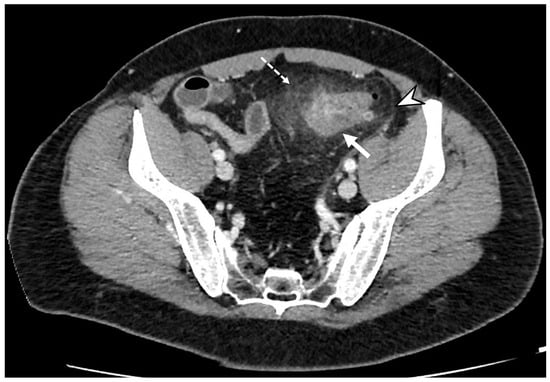

Figure 2. Axial contrast-enhanced CT images show wall thickening of the left colon (thick arrow) and the presence of perivisceritis, including the increased density of pericolic fat (fat stranding) (dotted arrow) and thickening of the left lateroconal fascia (so-called comma sign) (arrowhead).

An increased density of pericolic fat [fat stranding] and a small amount of pericolic fluid represent the main mesenteric findings, which, combined with the mural thickening, suggest a localized inflammatory process in uncomplicated diverticulitis (Figure 2) [10,12,13]. The degree of fat stranding can range from “dirty fat” to peridiverticular phlegmon. The phlegmon consists of an inflammatory mass, without walls, located near the inflamed colonic tract, round or oval in shape, and on CT, it presents with high attenuation compared to the mesenteric fat, without an enhancing wall (Figure 3) [3,5]. Multiplanar reconstruction allows for identifying minimum amounts of pericolic fat stranding in the case of horizontal colonic segments [12]. Pereira et al. suggest that the presence of “disproportionate” fat stranding concerning mural thickening suggests the diagnosis of diverticulitis [21]. A small amount of fluid on the root of the mesentery [comma sign] and thickening of the lateroconal fascia are additional signs of an inflammatory process (Figure 1) [13].